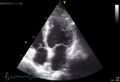

- BasicsOfImagingFig11.jpg 1,000 × 748; 45 KB

- BasicsOfImagingFig12.jpg 1,005 × 683; 46 KB